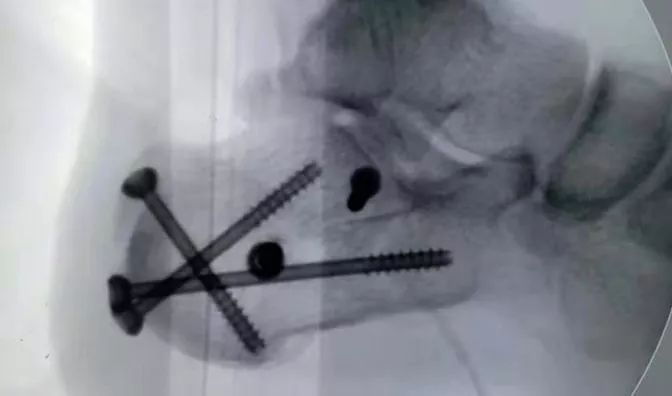

桂教授团队完美的通过

数个0.5cm长的小切口

将移位的骨块精准复位

并通过螺钉牢固固定

桂主任介绍,以往临床上通常采用关节镜技术来治疗跟骨骨折,但仅用于监控关节面的复位效果,不能做到全关节镜直视下复位。桂鉴超教授团队通过多点多方位关节镜下显露技术,360度清晰显露骨折线和关节面,取得关节面的精准解剖复位;再通过关节镜下定点造腔有限显露骨折线,全直视下清理骨折线和断端,轻松达到大切口手术才能完成的精准复位效果;由于是定点有限显露,通过关节镜技术到达窄小的空间,无需切开皮肤和皮下组织,因此创伤小,不会出现皮肤坏死和钢板外露的并发症。